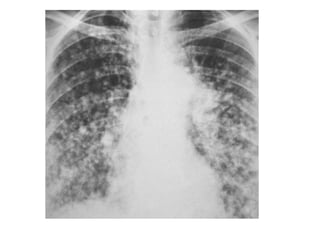

2-Interstitial Fibrosis (Asbestosis) :

-Features on chest radiographs include ground-glass

opacification, small nodular opacities, “shaggy” cardiac

silhouette, and ill-defined diaphragmatic contours, it has

been reported that 80% of patients with asbestosis have

coexistent pleural disease at chest radiography, fibrous

bands are sometimes seen to radiate inward from the

pleura

PA radiograph shows diffuse fine nodular and reticular opacification

with irregularity of mediastinal and diaphragmatic contours, the

costophrenic angles are blunted because of pleural thickening